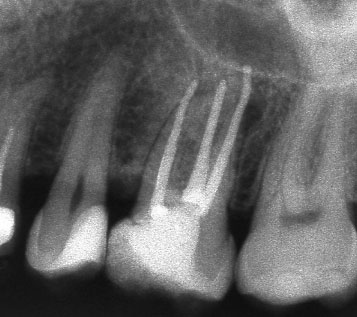

Винаги е необходимо лекуващият да се стреми към този резултат:

Понякога е налице патологичен процес около апекса на зъба, който налага да се проведе допълнителна хирургична намеса с цел отстраняване на лезията.